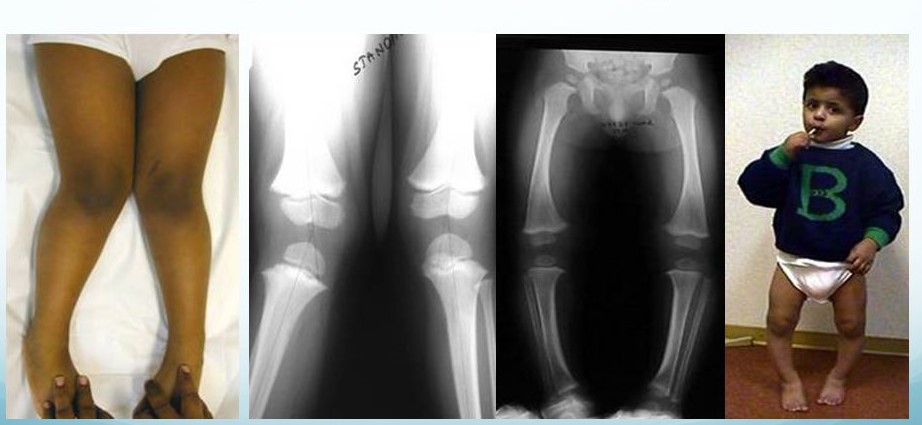

In most scenarios, its an over-concerned aunt or a nosy neighbour, who sets the alarm bells ringing in the parents minds. When they point out your child’s legs when in a gathering or a playground. Most Angular deformities around the knee, such as genu varum (bow legs) and genu valgum (knock knees), are common in children. These conditions refer to the inward or outward angling of the knees, which can be part of normal growth but sometimes require medical attention.

- Children with genu varum have knees that bow outward when the feet are together.

- It is normal in infants and typically corrects itself by age two.

- However, if the bowing persists beyond this age or worsens, it could indicate genuine varum.

Genu Varum (Bow Legs):

Genu Valgum (Knock Knees):

- In genu valgum, the knees angle inward, causing the feet to be apart when standing with the knees together.

- This condition is often seen in children between ages 2 and 5 and usually resolves on its own.

- Persistent or severe cases after age seven may suggest genuine valgum.

Early diagnosis is crucial for distinguishing between normal developmental variations and pathological conditions. Parents should consult a pediatric orthopedic surgeon if they notice persistent or severe bowing or knock-knee alignment, asymmetry between the legs, or associated pain and difficulty walking.